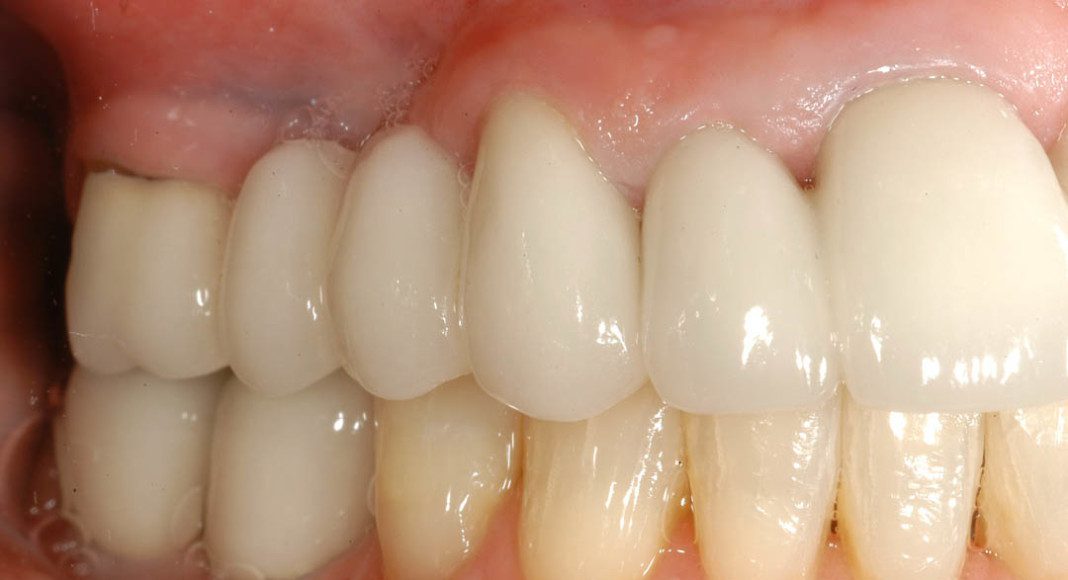

Pre-treatment, left lateral view. Notice the exposed margins of the old crowns from all the gum recession? These areas were very sensitive when she ate cold or sweet things. (We were able to correct that with the new crowns).